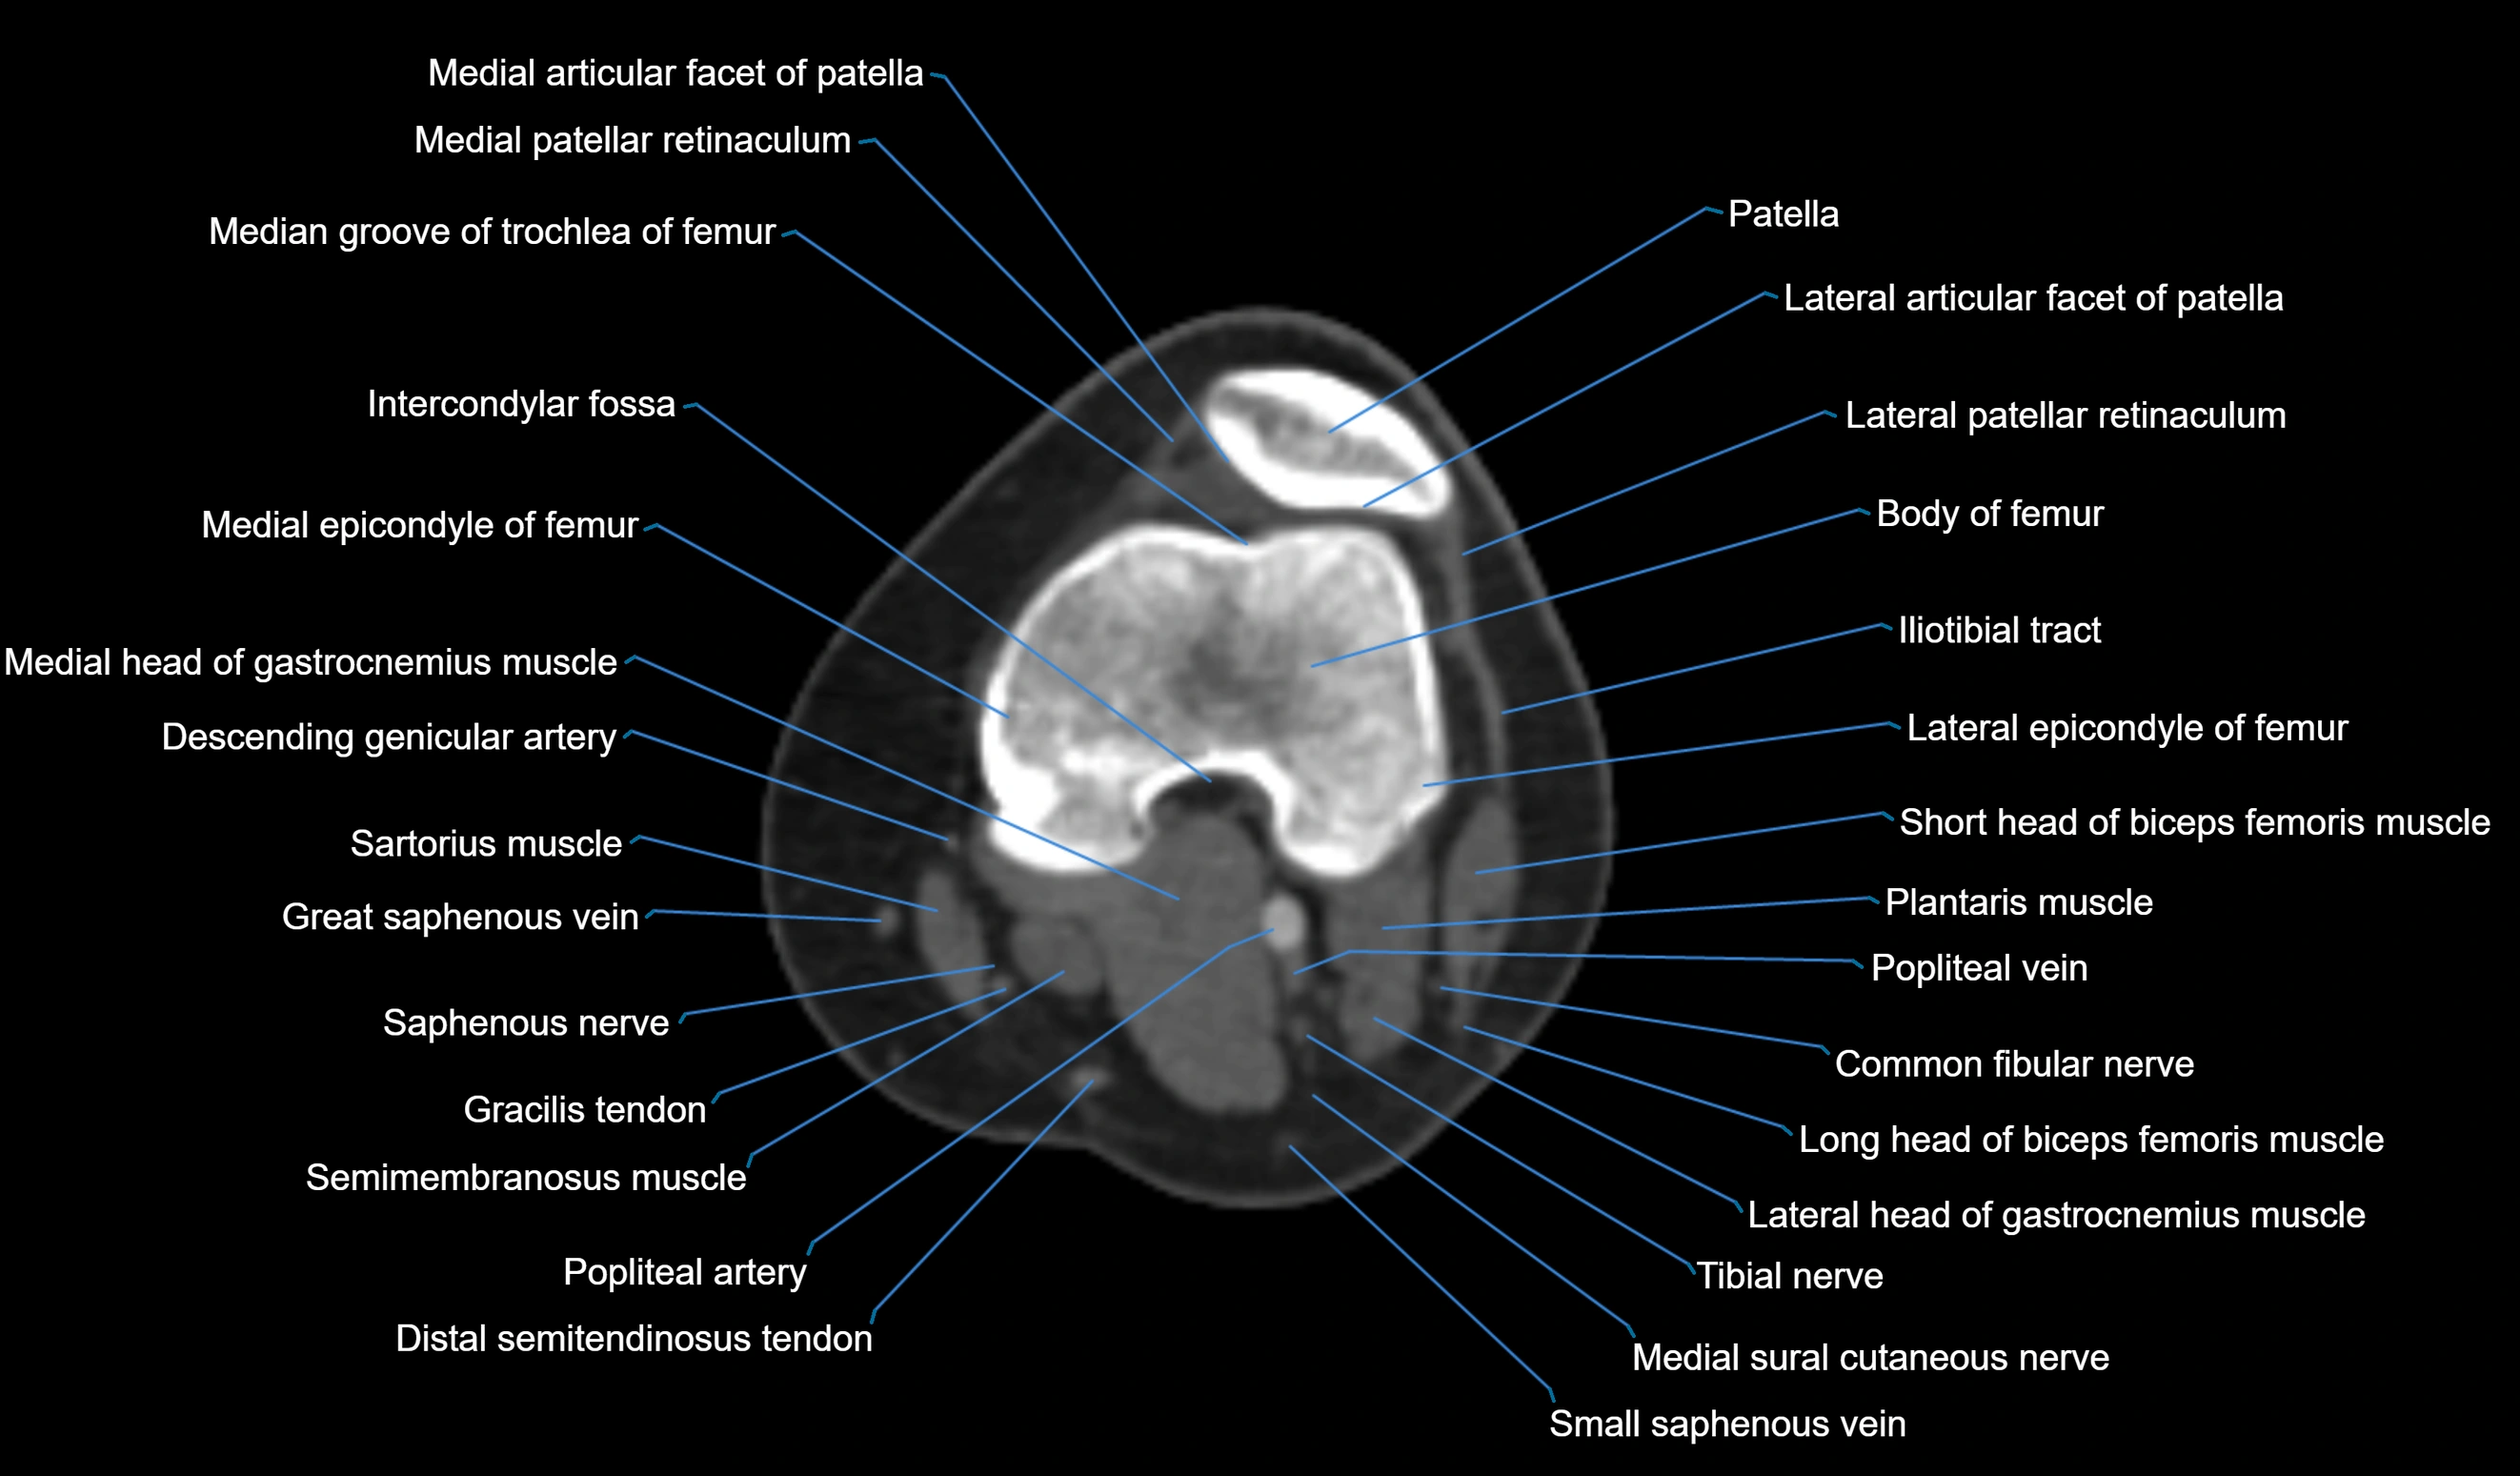

CT VRT 3D image

CT image